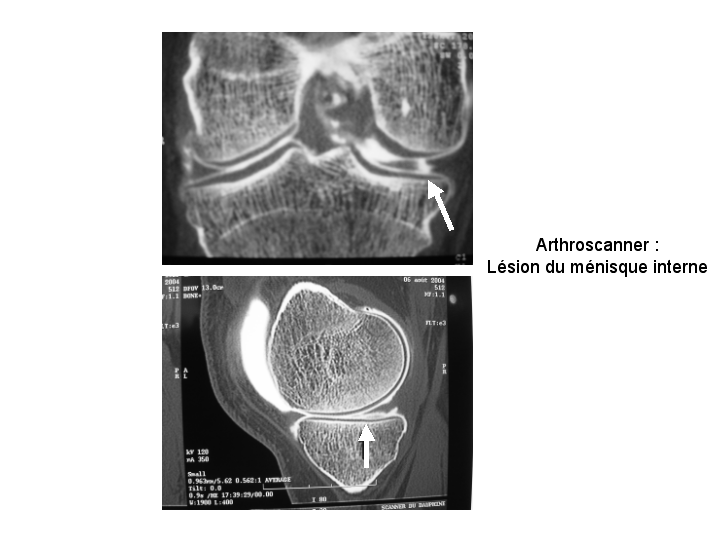

C’est un diagnostic qui est parfois difficile et qui nécessite alors de réaliser des examens complémentaires de type IRM ou arthroscanner.

L’intérêt de ces examens complémentaire est de préciser l’état du cartilage qui peut participer à la symptomatologie douloureuse.

En cas d’échec et/ou selon le type de lésion à l’IRM ou à l’arthroscanner : le traitement de la lésion méniscale par arthroscopie peut se discuter.